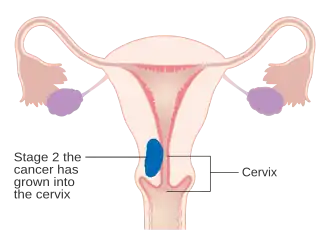

O carcinoma endometrial é estadiado cirurgicamente usando o sistema de estadiamento de cancro FIGO. O sistema de preparação do FIGO de 2009 é o seguinte:[56][57]

| Etapa | Descrição |

|---|---|

| I A | O tumor está confinado ao útero com menos da metade da invasão miometrial |

| IB | O tumor está confinado ao útero com mais da metade da invasão miometrial |

| II | O tumor envolve o útero e o estroma cervical |

| IIIA | O tumor invade a membrana serosa ou anexos |

| IIIB | Envolvimento vaginal e/ou parametrial |

| IIIC1 | Envolvimento do linfonodo pélvico |

| IIIC2 | Envolvimento de linfonodos para-aórticos, com ou sem envolvimento de linfonodos pélvicos |

| IVA | O tumor invade a mucosa da bexiga e/ou mucosa do intestino |

| IVB | Metástases distantes, incluindo metástases abdominais e/ou linfonodos inguinais |

A invasão miometrial e o envolvimento dos linfonodos pélvicos e para-aórticos são os padrões de disseminação observados com maior frequência.[2] Às vezes, é incluído um Estágio 0, neste caso denominado "carcinoma in situ".[9] Em 26% dos cancros presumivelmente em estágio inicial, o estadiamento intraoperatório revelou metástases pélvicas e à distância, tornando necessário um estadiamento cirúrgico abrangente.[25]

Cancro do endométrio em estágio IA e IB Cancro do endométrio em estágio II

Cancro do endométrio em estágio II Cancro do endométrio em estágio III